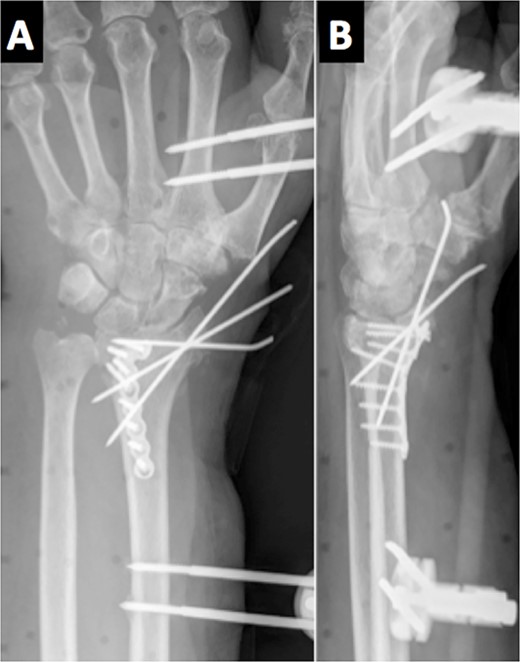

An 84-year-old, right-handed man attended the emergency room for the pain and swelling of his left wrist after a fall over his outstretched arm from a standing height. An X-ray was performed, showing an intra-articular comminuted fracture on the left distal radius, classified as 23-C3 according to the AO classification (Fig. 1). A cast was placed in the first place; meanwhile, the final treatment was decided.

The radiological images in the emergency department showed a comminuted intra-articular displaced fracture of the distal radius.